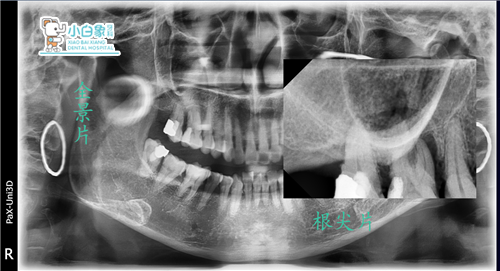

检查:口内查:16 二度松动,远中见白色充填物,探诊(-),叩诊(+),冷热诊正常,17 2度松动,探诊(-),叩诊(-),牙龈萎缩至根中三分之一,牙龈未见明显红肿,牙结石2度。

影像学检查:16 17见充填物影像。